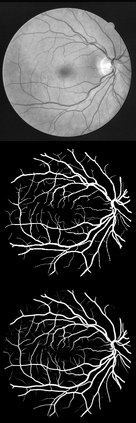

U-Net has been providing state-of-the-art performance in many medical image segmentation problems. Many modifications have been proposed for U-Net, such as attention U-Net, recurrent residual convolutional U-Net (R2-UNet), and U-Net with residual blocks or blocks with dense connections. However, all these modifications have an encoder-decoder structure with skip connections, and the number of paths for information flow is limited. We propose LadderNet in this paper, which can be viewed as a chain of multiple U-Nets. Instead of only one pair of encoder branch and decoder branch in U-Net, a LadderNet has multiple pairs of encoder-decoder branches, and has skip connections between every pair of adjacent decoder and decoder branches in each level. Inspired by the success of ResNet and R2-UNet, we use modified residual blocks where two convolutional layers in one block share the same weights. A LadderNet has more paths for information flow because of skip connections and residual blocks, and can be viewed as an ensemble of Fully Convolutional Networks (FCN). The equivalence to an ensemble of FCNs improves segmentation accuracy, while the shared weights within each residual block reduce parameter number. Semantic segmentation is essential for retinal disease detection. We tested LadderNet on two benchmark datasets for blood vessel segmentation in retinal images, and achieved superior performance over methods in the literature. The implementation is provided \url{https://github.com/juntang-zhuang/LadderNet}